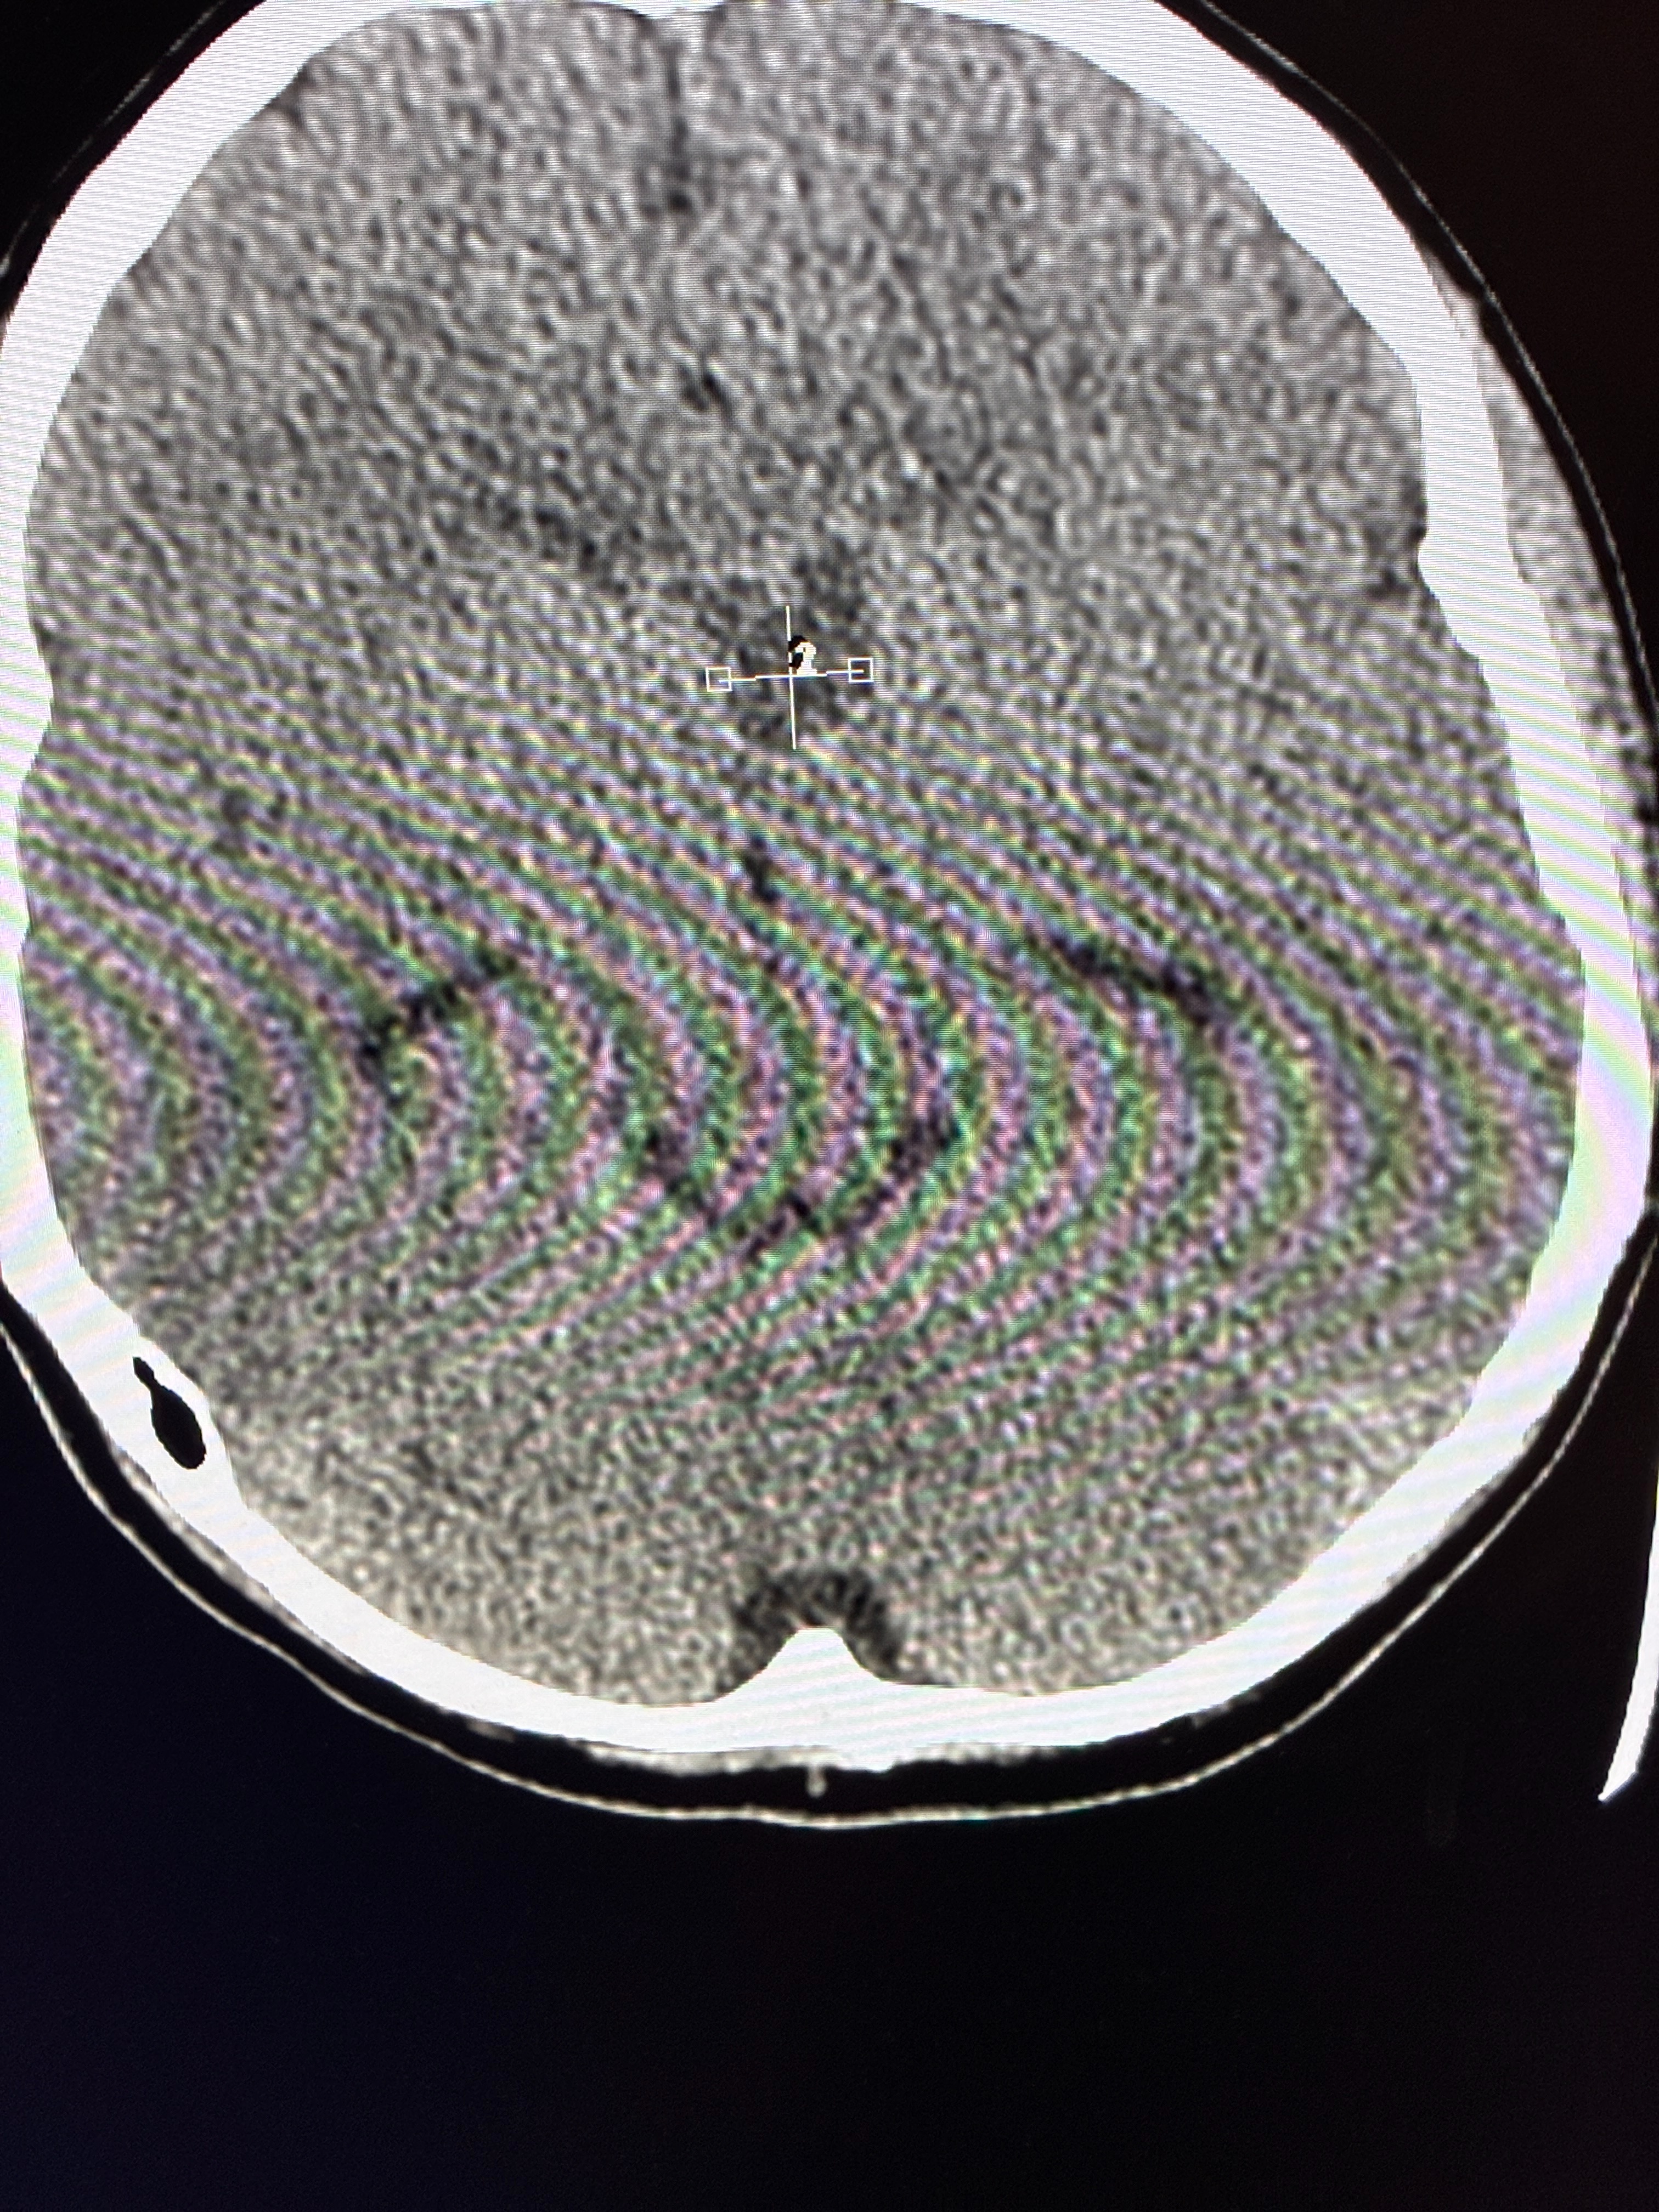

On January 10th, the Hinton family's lives were forever changed. Jack Hinton is an 18-year-old senior at Viewmont High School. Jack had just finished playing in a pickleball tournament. As he sat down to eat something, his entire right side suddenly became numb. He couldn't talk and slumped over. His dad, Kevin, quickly drove him to Lakeview Emergency Room, fearing a stroke. The doctors determined that Jack has a cancerous brain tumor called bifocal germinoma.